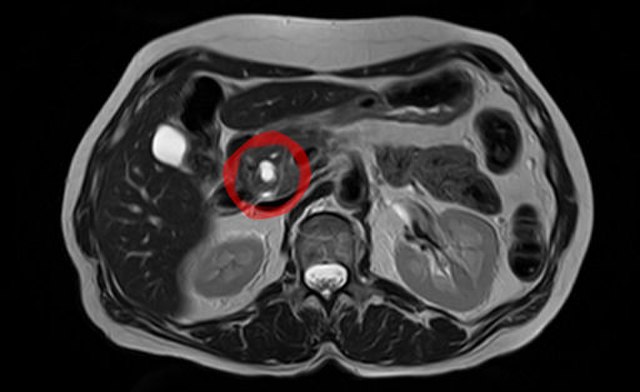

- Ressonância Magnética (RM) com Colangiopancreatografia por Ressonância Magnética (CPRM): Fornece imagens detalhadas do sistema de ductos pancreáticos e é especialmente útil para distinguir IPMN de outras lesões císticas.

No Consensos de Fukuoka foi determinado qual tamanho e outras características destes cistos nos exames de ecoendoscopia e colangiorressonância são os maiores determinantes de risco para câncer.

Dentre os fatores de maior risco para IPMN desenvolver um câncer de pâncreas são:

- presença de ictericia

- presença de áreas sólidas que retenham contraste maiores que 5mm

- dilatação do ducto pancreático principal acima de 10mm

- cistos maiores que 3cm

- paredes do cisto grossas

- alteração brusca do ducto pancreático

- presença de gânglios linfáticos aumentados na região

- valor de CA 19-9 aumentados

- crescimento maior que 5mm ao ano